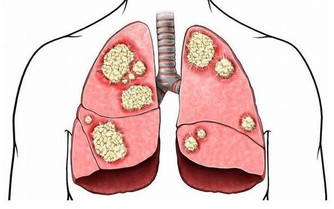

肝癌的凶險人人知之,它是我國常見的惡性腫瘤之一,死亡率很高,次於胃癌。

肝癌的發展,從第一個癌細胞在體內“誕生”開始,到患者身體出現明顯的不適,是非常漫長的一個過程。而在這漫長的過程裡,絕大部分的肝癌患者都不會出現異常,只有極少數患者可能出現食慾降低、上腹脹悶、腹痛等異常。